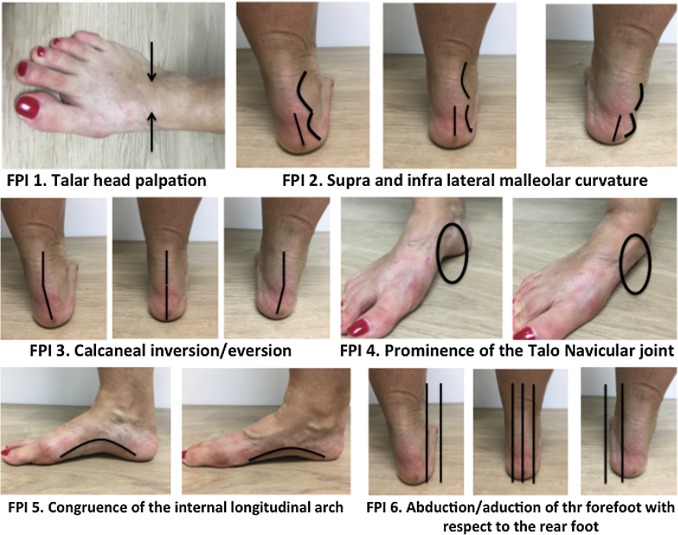

Identify areas where you feel pressure, burning, or pain. Note it during walking, running, or standing.

Stand barefoot and look at your feet from the back. If the ankles roll inward or outward, that may indicate pronation/supination.